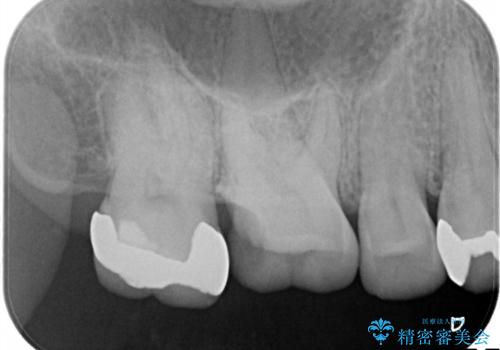

銀歯が外れてしまった ゴールドインレーによる補綴治療

- 銀歯が外れて、中が虫歯になっているところがありました。

虫歯を取り除き、ゴールドインレーを装着する治療計画としました。

ゴールドは目立つという欠点がありますが、適合が良く、割れることもないため、長期的に安定した治療法となります。